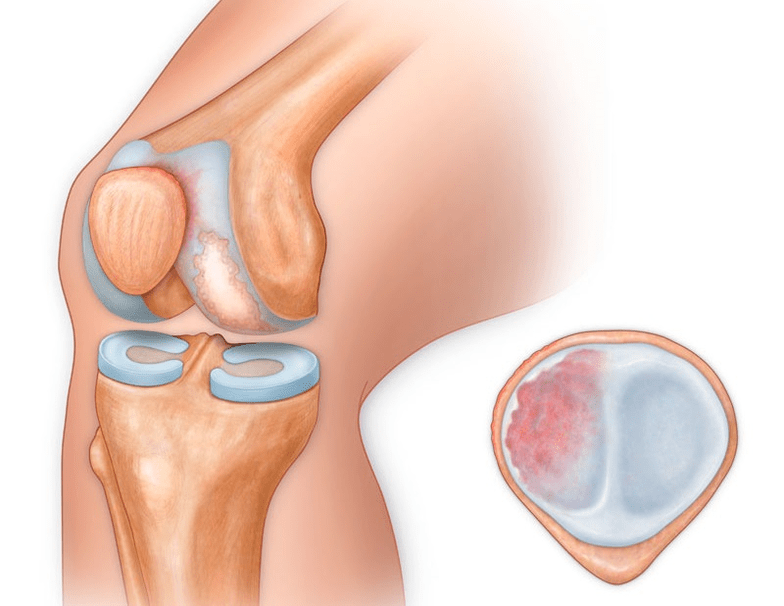

In addition to the inner or outer part of the knee, osteoarthritis can also affect the surfaces between the patella and the intercondylar groove of the femur.This option is calledpatellofemoral arthrosis.

The cause is usually subluxation, fracture, or lateralization of the patella.